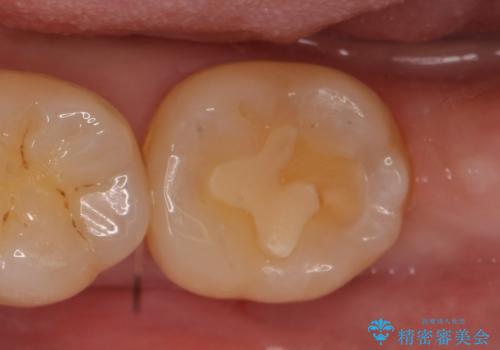

ゴールドインレーにも2次虫歯 再びゴールドインレーにてやり直し

白金加金合金や金合金にて製作された歯科修復物は適合性がよく、安定した材質であるため、2次的な虫歯が生じづらいのですが、もともと虫歯が取り残されていたり、お手入れが悪いとやり直しが必要なこともあります。

詰め物の種類:PGA In